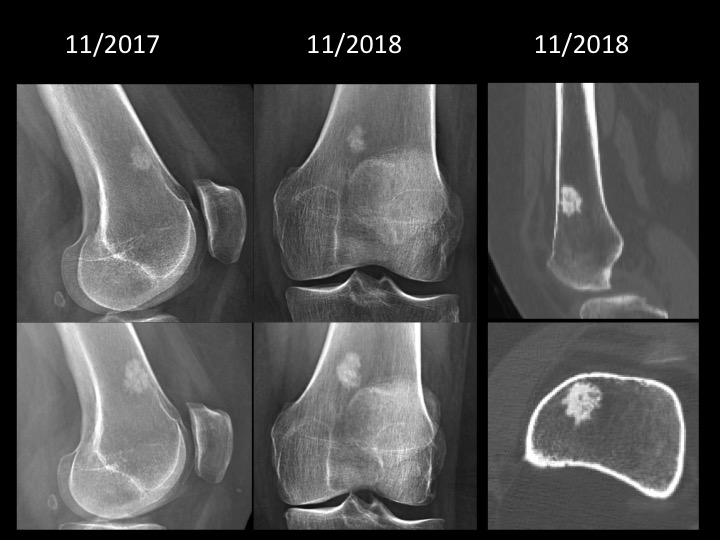

Figure 2 for case bone island ( RID4004 )

Figure 2

Never seen a bone island de novo and growing so fast. CT attenuation in 900HU range, compatible with bone island. Would you have felt comfortable watching it?

Diagnosis

bone island ( RID4004 )